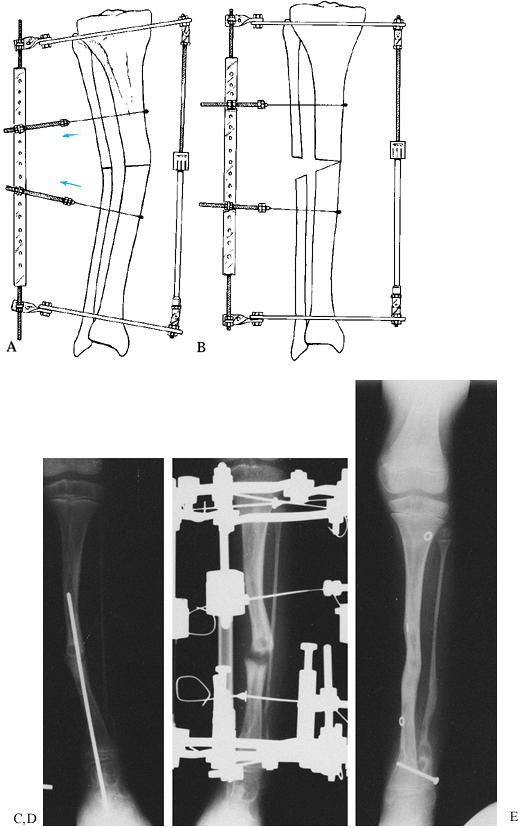

![]() |

Figure 32.26.

Varus malunions of the femur are illustrated with and without aggravating or compensatory translation. Notice that in the femur, translation toward the convexity is aggravating, whereas translation toward the concavity is compensatory. The reason for this is that by convention we refer to translation as the distal fragment being translated relative to the proximal. If we think of the proximal fragment of the femur as the one that is translating, then the rules are similar to that described in the tibia (Fig. 32.25). Notice that the translational deformity shifts the true apex of the deformity either proximal or distal to the apparent apex at the level of the malunion. |

Figure 32.27. A: Varus malunion of the mid diaphysis of the tibia with compensatory lateral translation. B:

The frame was applied with the hinges at the level of the true apex of the deformity, and the corticotomy was carried out at that level. C: Distraction of the concavity led to realignment of the tibia through an open-wedge correction. Notice the simultaneous correction of the angulation and translation, as demonstrated by the colinearity of the medial tibial diaphysis. The hinges are now straight and the rings are parallel, indicating completion of the deformity correction. D: After completion of the angular correction, the parallel rings were distracted to lengthen the tibia. E: Final AP standing radiograph demonstrates the alignment of the corrected malunion. There is a persistent leg-length discrepancy of 2 cm, which was accepted because of slow healing in this patient. |